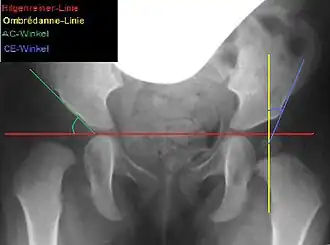

Lateral coverage is measured using the acetabular angle (AC angle) on a pelvic X-ray, defined as the angle between a horizontal line through the Y-sutures and a line along the acetabular rim. In healthy newborns, the AC angle is approximately 25°, decreasing to about 15° by age 6 and 11–12° by age 12.[6] Acetabuloplasty aims to correct the AC angle to these physiological values, achieving an anatomical reconstruction.[6]